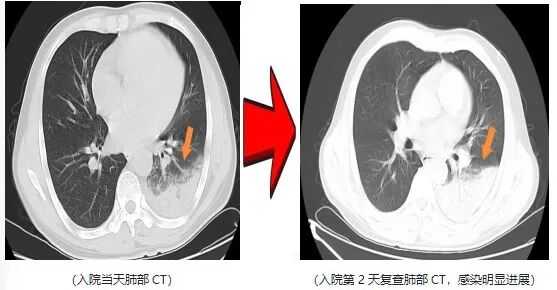

近日,一名爱鸟人士因持续高热、剧烈咳嗽,紧急就诊并收治于杭州萧山区中医院呼吸内科。入院后予以常规抗感染治疗2天,患者高热症状仍反复,最高体温升至40.5℃,伴干咳气促、夜间难以入眠,病情进展后更出现咯血及呼吸衰竭表现。

鉴于患者病情呈重症化趋势,在排除急性肺栓塞等支气管镜检查禁忌证后,医院呼吸内科团队第一时间为患者完善支气管镜检查,同步采集肺泡灌洗液行病原学宏基因组测序,最终锁定致病“元凶”——鹦鹉热衣原体 ,该病原体正是源于患者饲养的宠物鹦鹉。

明确病因后,医护团队予针对性特效药物干预。仅2天后,患者体温恢复正常,干咳气促、咯血及呼吸衰竭等症状均显著缓解,后续顺利康复出院。